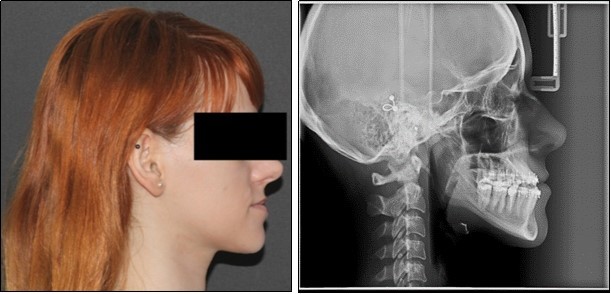

Orthodontic examination digital photographs were taken before the patient underwent the initial cinical examination. Frontal esthetic analysis revealed a long face, an increased third floor of the face and an asymmetry due to mandibular deviation to the left. Lateral view analysis disclosed a concave profile, with a deficient nasomaxillary area and proeminent chin. The lower lip was protruded, the upper lip was retruded and the mentolabial anlge was reduced. (Figure 1)

Figure 1.Initial extraoral photographs